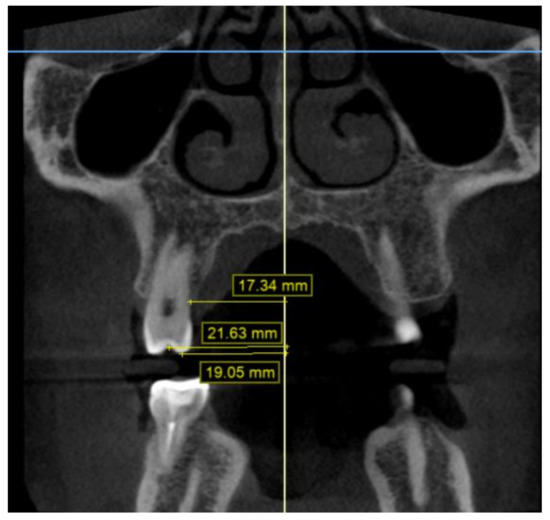

2.2. Methodology of Measurements